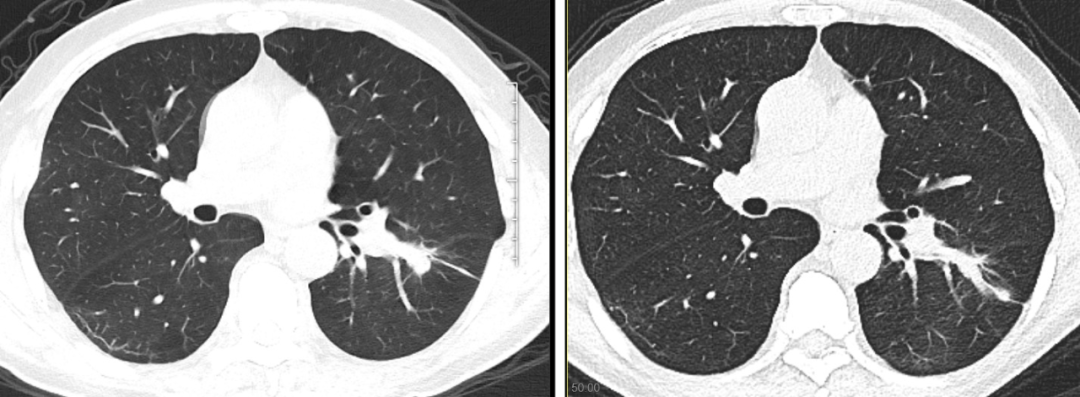

手术过程顺利,术后李大伯表示手术全程舒适,术后1个月后复查,肺内病灶较术前明显吸收。

李大伯术前术后肺部病灶对比图